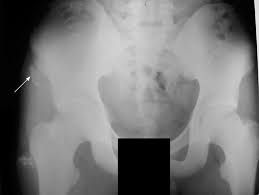

Anterior Superior Iliac Spine, Appendicular Skeleton And Joints Ppt Download : It can be palpated by putting the hands at the top of the hipbones and following the bony margins toward the front of the hips.. The posterior border of the ala, shorter than the anterior, also presents two projections separated by a notch, the posterior superior iliac spine and the posterior inferior iliac spine. Jun 28, 2021 · insertion: Asis, anterior superior iliac spine. Diagnosis is made with pelvis radiographs that shows an avulsion off the aiis. Anterior angulation of the coccyx may be a normal variant but poses a diagnostic challenge for those considering coccygeal trauma.

It provides attachment for the inguinal ligament , the sartorius muscle , 1 4 and the tensor fasciae latae muscle. The anterior superior iliac spine (asis) is the most anterior part of the iliac crest. An anterior superior iliac spine (asis) avulsion is a traumatic avulsion of the asis due to a sudden and forceful contraction of the sartorius and tensor fascia lata that occurs in young athletes. Asis, anterior superior iliac spine. This part is the most observable and palpable of the pelvis. The posterior border of the ala, shorter than the anterior, also presents two projections separated by a notch, the posterior superior iliac spine and the posterior inferior iliac spine. Diagnosis is made radiographically with displaced injuries but ct/mri may be required to diagnosis nondisplaced fractures. It provides attachment for the inguinal ligament, and the sartorius muscle. An anterior inferior iliac spine (aiis) avulsion is an apophyseal avulsion injury seen in adolescent athletes as a result of eccentric contraction of the rectus femoris. It refers to the anterior extremity of the iliac crest of the pelvis. The anterior superior iliac spine refers to the anterior extremity of the iliac crest of the pelvis. Outer lip of anterior iliac crest, anterior superior iliac spine (asis) insertion: Classification four types of coccyx have been described:

Outer lip of anterior iliac crest, anterior superior iliac spine (asis) insertion: Aug 29, 2017 · aiis, anterior inferior iliac spine; Asis, anterior superior iliac spine. The posterior border of the ala, shorter than the anterior, also presents two projections separated by a notch, the posterior superior iliac spine and the posterior inferior iliac spine. An anterior superior iliac spine (asis) avulsion is a traumatic avulsion of the asis due to a sudden and forceful contraction of the sartorius and tensor fascia lata that occurs in young athletes. The tensor fasciae latae and sartorius muscles of the thigh have their origins at the anterior superior spine. An anterior inferior iliac spine (aiis) avulsion is an apophyseal avulsion injury seen in adolescent athletes as a result of eccentric contraction of the rectus femoris. It provides attachment for the inguinal ligament, and the sartorius muscle. The posterior superior iliac spine serves for the attachment of the oblique portion of the posterior sacroiliac ligaments and the multifidus. It provides attachment for the inguinal ligament , the sartorius muscle , 1 4 and the tensor fasciae latae muscle. It can be palpated by putting the hands at the top of the hipbones and following the bony margins toward the front of the hips. Classification four types of coccyx have been described: Diagnosis is made radiographically with displaced injuries but ct/mri may be required to diagnosis nondisplaced fractures.

The coccyx is curved slightly forward, with its. It can be palpated by putting the hands at the top of the hipbones and following the bony margins toward the front of the hips. Outer lip of anterior iliac crest, anterior superior iliac spine (asis) insertion: Diagnosis is made with pelvis radiographs that shows an avulsion off the aiis. Jun 09, 2015 · at the posterior end of the ilium, the iliac crest narrows before terminating at another bony process known as the posterior superior iliac spine. Anterior angulation of the coccyx may be a normal variant but poses a diagnostic challenge for those considering coccygeal trauma. Anterior aspect of greater trochanter of femur innervation: It provides attachment for the inguinal ligament , the sartorius muscle , 1 4 and the tensor fasciae latae muscle. The posterior superior iliac spine serves for the attachment of the oblique portion of the posterior sacroiliac ligaments and the multifidus. The tensor fasciae latae muscle attaches to the lateral aspect of the superior anterior iliac spine, and also about 5 cm away at the i. An anterior superior iliac spine (asis) avulsion is a traumatic avulsion of the asis due to a sudden and forceful contraction of the sartorius and tensor fascia lata that occurs in young athletes. Thigh abduction, thigh internal rotation (anterior part); Jun 28, 2021 · insertion: